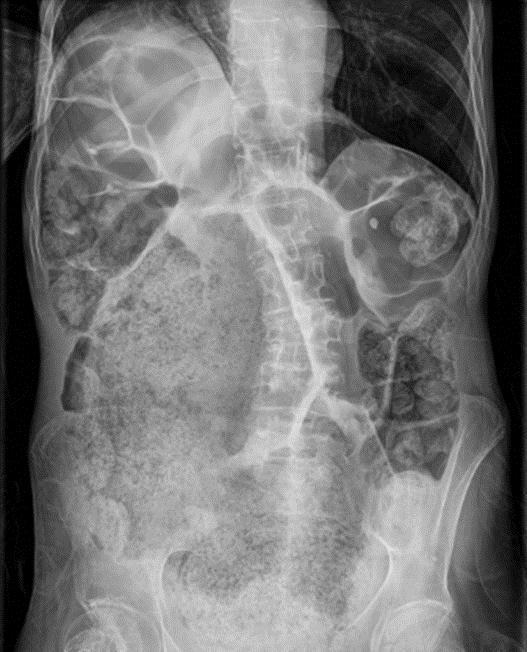

Por ejemplo, la carcinomatosis peritoneal secundaria a adenocarcinoma de colon es una metástasis al peritoneo poco frecuente e indicativa de mal pronóstico.

Radiografía simple de abdomen: silencio central con desplazamiento de asas intestinales hacia la periferia.